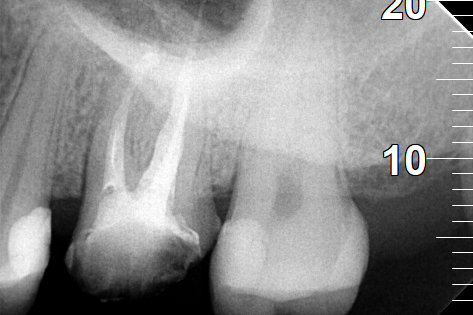

Root canal retreatment

BEFORE

BEFORE

The metallic stift after removing it from the tooth